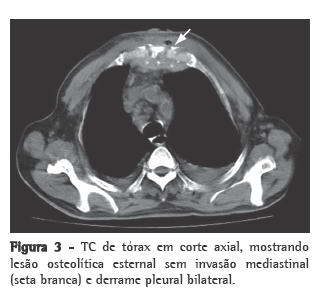

Homem de 74 anos, branco, agricultor aposentado, não-tabagista e ex-etilista, apresenta-se com dor torácica na porção superior do esterno iniciada há um ano com edema e eritema local, agravada há duas semanas com fístula que drenava secreção purulenta. Ainda referia febre vespertina, sudorese noturna e emagrecimento de aproximadamente 25 kg nos últimos 12 meses. O paciente fazia acompanhamento ambulatorial em várias unidades do Hospital Universitário de Santa Maria por apresentar múltiplas comorbidades: hipertensão arterial sistêmica, insuficiência cardíaca, valvulopatia mitral, hipertensão arterial pulmonar, hipotireoidismo, insuficiência renal crônica, além de uma colite inespecífica e hiperplasia benigna de próstata. Estava em uso de furosemida, sinvastatina, omeprazol, levotiroxina, hidralazina, clonazepam, sertralina, finasterida e doxazosina. Ao exame físico de admissão, o paciente estava em regular estado geral, com mucosas intensamente descoradas, pressão arterial de 130/80 mmHg, frequência cardíaca de 80 bpm, temperatura axilar de 36°C e frequência respiratória de 35 ciclos/min. Apresentava um sopro sistólico 3+/6+ em ápice cardíaco com irradiação axilar e murmúrio vesicular diminuído em ambas as bases pulmonares. Na região do manúbrio esternal, havia uma área de aproximadamente 10 cm de diâmetro, hiperemiada, edemaciada, mal delimitada, dolorosa à palpação, apresentando fístula com drenagem de secreção purulenta (Figura 1). Foi coletado um swab da lesão e realizada biópsia esternal por cirurgia aberta para a análise histopatológica e iniciado ciprofloxacina e clindamicina. O hemograma evidenciava anemia normocítica e normocrômica, o teste PPD demonstrou uma enduração de 15 mm, o exame anti-HIV (ELISA) foi negativo, e a velocidade de hemossedimentação (VHS) era 48 mm/h na primeira hora. Foram realizados exames de imagem (radiogramas de tórax frontal e perfil) que não evidenciaram imagens pleuropulmonares sugestivas de TB prévia ou ativa. O radiograma de perfil da região esternal revelou uma lesão osteolítica na região do manúbrio e dos primeiros arcos costais (Figura 2). A TC de tórax evidenciou lesão osteolítica do manúbrio esternal, sem invasão mediastinal, além de derrame pleural bilateral transudativo relacionado ao quadro clínico de hipertensão pulmonar e insuficiência cardíaca descompensada (Figura  3). Ainda procedeu-se à cintilografia trifásica com tecnécio, que não mostrou captação aumentada do radiotraçador pela lesão. O swab revelou cocos gram-positivos aos pares, e a cultura foi positiva para Staphylococcus aureus multissensível e negativa para fungos ou micobactérias após 70 dias de incubação. O regime antibiótico foi alterado para oxacilina. O resultado do exame histopatológico da lesão esternal demonstrou granuloma caseoso. Foi realizada uma nova biópsia esternal para a realização da PCR (Laboratório Álvaro, Cascavel, PR, Brasil) e iniciada terapia empírica contra TB com o esquema I (rifampicina, isoniazida e pirazinamida) com boa resposta terapêutica. A PCR foi positiva para Mycobacterium ­tuberculosis, confirmando o diagnóstico de osteomielite esternal tuberculosa.

Sob o ponto de vista radiológico, a TB esternal pode se apresentar com os seguintes padrões de destruição óssea: lesões osteolíticas, reação periosteal, padrões de realce e abscesso de partes moles com ou sem formações cálcicas internas.(6) Esses achados não são exclusivos, podendo ser encontrados em infecções agressivas como a actinomicose.(8) A TC não demonstra aparente vantagem em relação ao radiograma esternal para a avaliação do comprometimento ósseo, mas mostra-se muito superior na avaliação dos tecidos moles perilesionais e o envolvimento mediastinal e pulmonar.(5-9) A ressonância magnética é uma boa opção para a avaliação tanto de tecidos moles quanto das lesões ósseas, demonstrando alterações precoces da medula óssea, especialmente em estágios precoces com radiograma normal.(4,5,9) A cintilografia trifásica com tecnécio tem alta sensibilidade e especificidade para o diagnóstico de osteomielite.(2,4) No caso apresentado, o paciente não apresentou captação esternal aumentada do radiotraçador nem fotopenia na lesão osteolítica ou outros achados compatíveis com osteomielite.